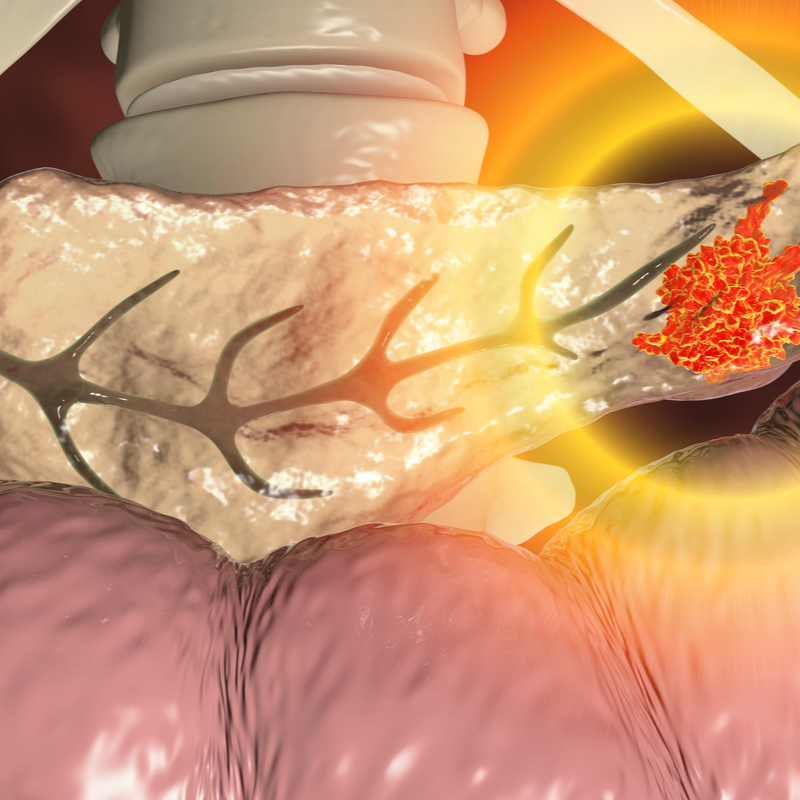

Syringomyelia

Ependymoma